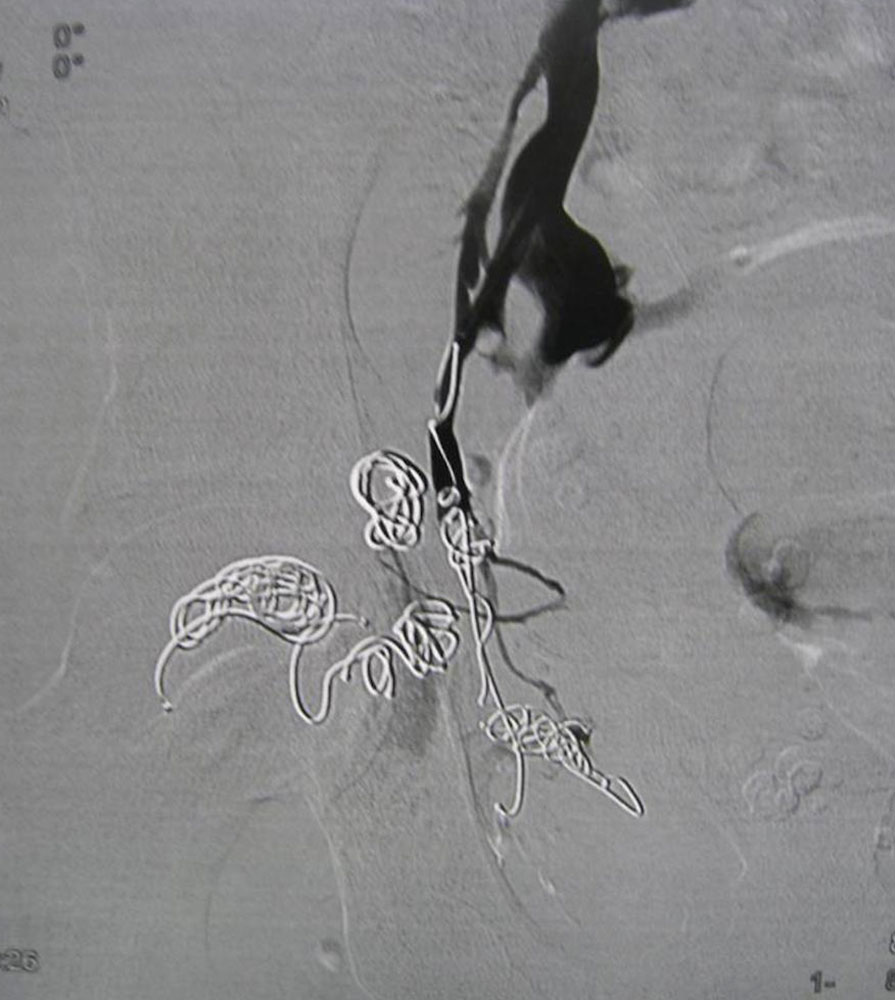

Embolization of communicating veins

The catheter-assisted insertion of thrombogenic materials such as coils, glue and plugs is a possible option in the therapy of large-lumen and deep venous malformations. The main purpose of this method is to close large veins communicating with the deep vein system.

Although this does not “dry out” the entire malformation, it can be useful to close the communication of a particularly large-lumen part of it with the deep venous system. Subsequent sclerotherapy can then be carried out effectively and without complications, without the sclerosing agent being able to drain off. The embolization is intended to reduce the blood volume of the affected body part and thus the associated, troublesome tightness. However, the radiologically detectable success of the intervention is not always reflected in the clinical outcome.

After successful embolization, the symptoms can be very varied: improved, unchanged or even worse. The value of embolization should not be diminished by this statement. Instead it means that experience with the indication still needs to be gathered.